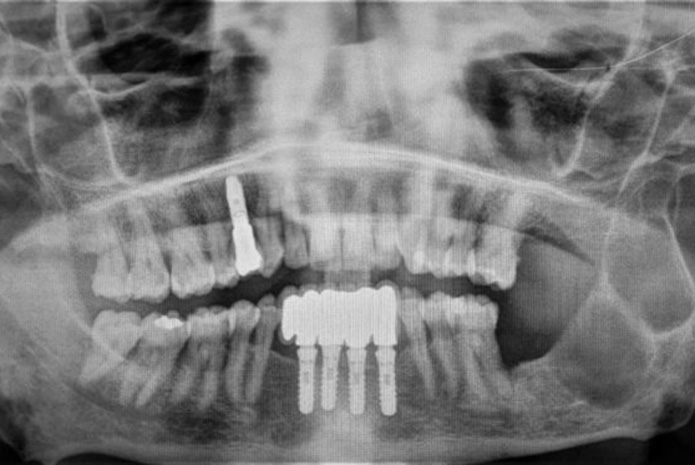

A continuación, se describe el caso clínico de una paciente en la sexta década de su vida, que presenta un queratoquiste odontogénico gigante en la región de la rama mandibular izquierda, con extensión hasta el cóndilo y apófisis coronoides. La lesión fue tratada con técnica de enucleación, con posterior legrado del lecho óseo y colocación de tubo de drenaje que se retiró a las tres semanas.